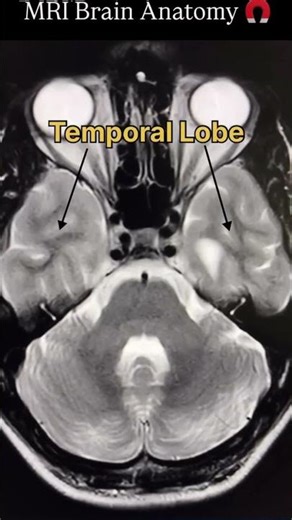

- MRI Brain

Imaging - Normal Brain

Brain MRI - MRI Anatomy

Brain Anatomy MRI - MRI Scan Brain